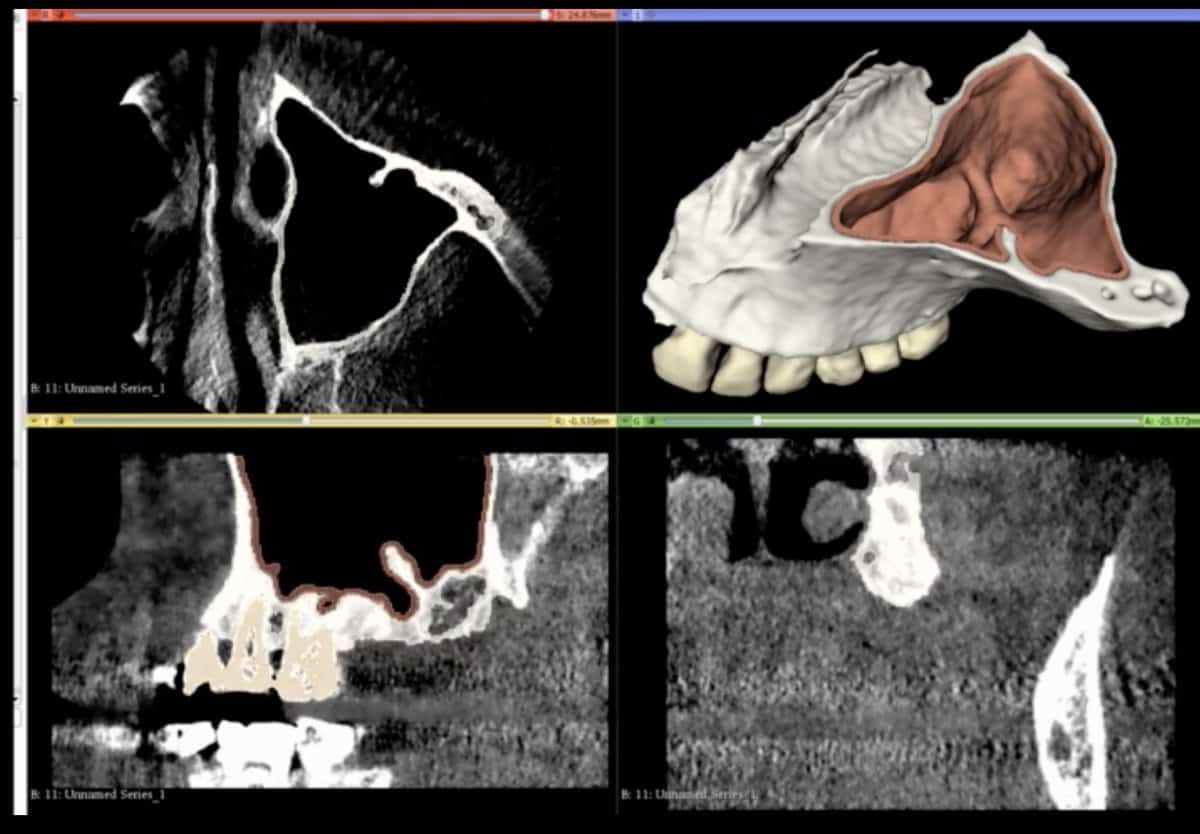

CBCT and Segmentation

Data from the CBCT are carefully segmented into the different tissue

Tissue definition

Bone, teeth, soft tissue, Schneiderian membrane are defined and represented

Anatomic representation

Precise anatomic reproduction of the actual surgical anatomy is designed

A Challenging surgical case with a complex of vertical and horizontal septa in the posterior sinus. Segmentation of the 3D radiographical and optical data and 3D printing in multiple layers from AMMA Ltd Hong Kong, has allowed for an accurate representation of the anatomy where multiple surgical access approaches were tested.